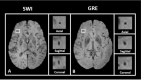

Cerebral microbleeds, observed as small, spherical hypointense regions on gradient echo (GRE) or susceptibility weighted (SWI) magnetic resonance imaging (MRI) sequences, reflect small hemorrhagic infarcts, and are associated with conditions such as vascular dementia, small vessel disease, cerebral amyloid angiopathy, and Alzheimer's disease. The current gold standard for detecting and rating cerebral microbleeds in a research context is visual inspection by trained raters, a process that is both time consuming and subject to poor reliability. We present here a novel method to automate microbleed detection on GRE and SWI images. We demonstrate in a community-based cohort of older adults that the method is highly sensitive (greater than 92% of all microbleeds accurately detected) across both modalities, with reasonable precision (fewer than 20 and 10 false positives per scan on GRE and SWI, respectively). We also demonstrate that the algorithm can be used to identify microbleeds over longitudinal scans with a higher level of sensitivity than visual ratings (50% of longitudinal microbleeds correctly labeled by the algorithm, while manual ratings was 30% or lower). Further, the algorithm identifies the anatomical localization of microbleeds based on brain atlases, and greatly reduces time spent completing visual ratings (43% reduction in visual rating time). Our automatic microbleed detection instrument is ideal for implementation in large-scale studies that include cross-sectional and longitudinal scanning, as well as being capable of performing well across multiple commonly used MRI modalities.